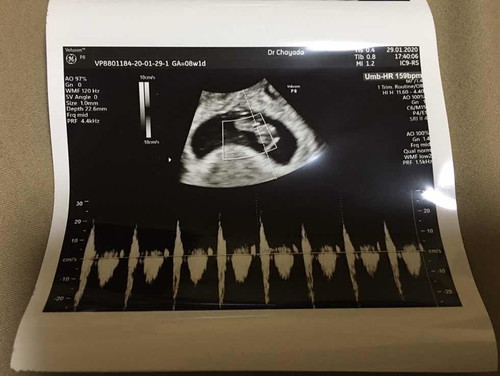

เห็นหลายๆเคสเลือดออก แต่แม่ๆก็ยังไม่รีบไปหาหมอเห็นแล้วก็อดเป็นห่วงไม่ได้ว่าทำไมไม่รีบไปหาหมอก่อน ประสบการณ์เราเองจะช่วยแก้ปัญหาทุกอย่าง ตัวเราเองก็เลือดออก แต่เลือดไม่ได้สดไม่ได้แดง เรายังกลัวลูกจะหลุดเลยโดนแอดมิดไป 1 คืน วันที่ 2 จะแอดมิดอีกแต่หมอก็บอกสาเหตุไม่ได้ ตัดสินใจเข้าเมืองไปตรวจกับหมอสูติดีกว่า ซาวด์ผ่านช่องคลอด ผลออกมาน้องยังปลอดภัย แข็งแรง เกาะแน่นมาก หัวใจเต้นปกติ 159ครั้งต่อนาที ในอายุครรภ์ 8วีค1วัน โชคดีเลือดที่ออกอยู่คนละฝั่งกับที่ลูกเกาะ หมอก็บอกไม่ได้ว่าเลือดออกเพราะอะไรแต่เลือดจะหยุดไหลไปเอง